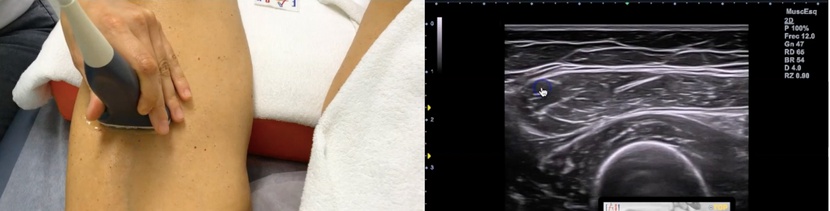

Te enseñamos cómo debe ser la exploración ecográfica en la normalidad del recto anterior y qué imágenes puedes encontrarte en una persona con el recto anterior roto.

ECOGRAFÍA DE UN RECTO ANTERIOR SANO

Vamos a tener en cuenta el siguiente corte de referencia.

El corte transversal es elprimer corte que debes hacer, te va a permitir ubicarte en el espacio e identificar con mayor rapidez al recto anterior. Su arquitectura es un tanto atípica.